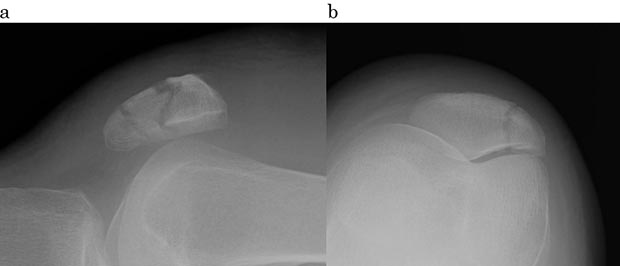

図1の様に、膝蓋骨が骨折すると、それを包んでいた大腿部の腱によって引き裂かれた、2つあるいはそれ以上の骨のカケラに割れ、自分の意思ではうまく膝が動かせなくなります。そして膝が激しく腫れ、押さえると非常に痛みを感じるようになります。場合によっては、皮膚の表面から骨折した骨のカケラの一部や引き裂かれた骨のカケラの隙間を触ることができます。

図1 受傷時の膝蓋骨骨折。折れた骨のカケラが引き裂かれている。

a: X線側面画像。3つのカケラに割れている。

b: 別方向(軸位)画像。縦状に割れている。